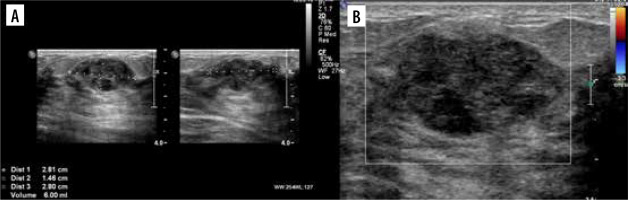

Figure 9

Two ultrasound (US) examinations of breast metastases in Patient no. 4. A, B) Initial examination in our centre. A) The largest nodule in the left breast. B) The largest nodule in the right breast. C, D) The second US after the 4th cycle of chemotherapy. Partial regression of the lesions. C) Nodule in the left breast. D) Nodule in the right breast

The patient was qualified for chemotherapy (VAC), and partial regression of the metastatic and primary lesions was initially achieved (Figures 9C and D).

The patient was admitted to our centre for further diagnosis and treatment. On US almost complete involvement of both breasts by heterogeneous, irregularly vascularised nodules was described; in the left breast, the largest ones were located centrally, and had approximately 78 × 73 × 86 mm on the left and 50 × 35 × 42 mm on the right (Figures 9A and B). Additionally, numerous enlarged lymph nodes and a metastasis in the mastoid attachment of the right sternocleidomastoid muscle were found. WB-MRI revealed multiple lesions consistent with metastases throughout the body. On PET-CT, all of them showed increased metabolism of 18F-FDG.